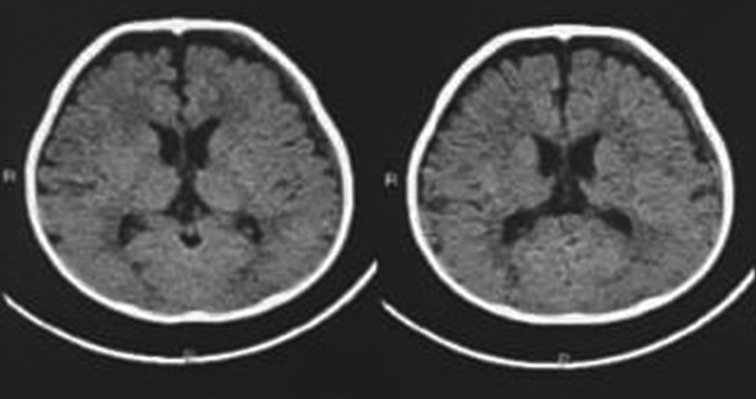

Acute subdural hematoma (ASDH) is a type of intracranial hemorrhage and is due to the collection of blood below the inner layer of the dura but external to the brain and arachnoid membrane. It tends to occur in the temporal parietal regions. Early intervention is the key for better outcome of the patient. Management depends on neurological status and imaging. Large SDH collects along the convexity of the brain causing compression over the brain stem with midline shift. In cases of conservatively managed ASDH, spontaneous resolution usually takes weeks to months depending on the size of the bleed. In rare cases, spontaneous rapid resolution of the SDH occurs. So here, we are presenting an 11-month-old baby girl who was brought to our Emergency room/department (ER) with a history of fall and computed tomography scan was suggestion of an ASDH in the left temporoparietal region which resolves on its own in 6 h which is a rare phenomenon and needs to be highlighted.